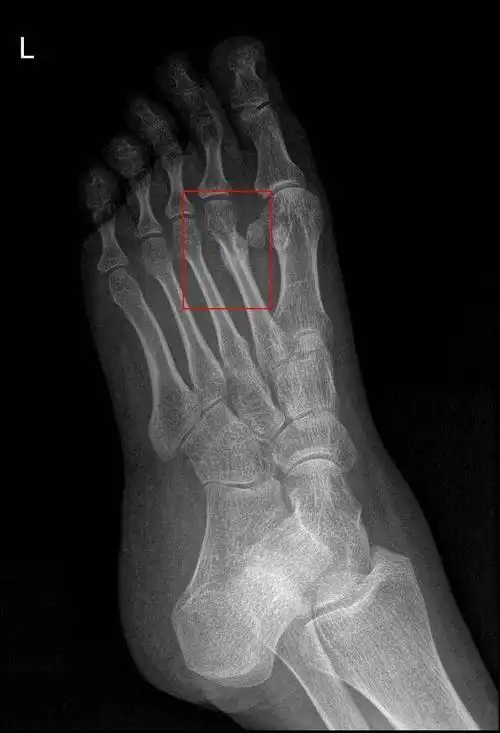

腕舟骨骨折